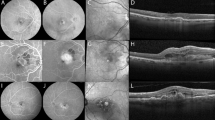

Abnormal retinal neovascularization caused by ischemic retinal vein occlusion (RVO) is a frequent cause of visually significant vitreous hemorrhage. The early detection of new vessels may be challenging and often requires the use of invasive tests such as fundus fluorescein angiography (FA). We demonstrate the use of wide-field optical coherence tomography angiography (WF-OCTA) in the detection and characterization of neovascularization secondary to ischemic RVO.

In the included 39 eyes with ischemic RVO, neovascularization elsewhere (NVE) was encountered in 16 of 39 eyes (41%) on WF-OCTA and were characterized as sea-fan type vessels and nodular type vessels, based on their appearance and localization. NVE was identified in 4/39 eyes on standard clinical examination, equating to a detection rate of 10.3%. All were of a sea-fan morphology. In one case, NVE found on WF-OCTA was not observed on UWF-FA, which was a nodular type. Neovascularization of the disc (NVD) was detected in one eye.

WF-OCTA may become a useful noninvasive tool in the detection of neovascularization in patients with ischemic RVO. Furthermore, the characterization of different morphologies of neovascularization detected by WF-OCTA could be of clinical relevance